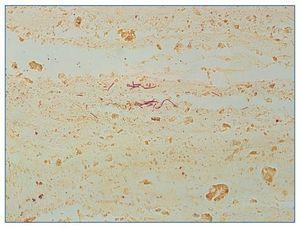

A su llegada a nuestro centro, la paciente es valorada conjuntamente por urología y nefrología, y se decide la realización de trasplantectomía urgente ante la escasa viabilidad del injerto y el estado hemodinámico de la paciente. Se realiza disección extraperitoneal hasta identificar cápsula renal, que se incide, obteniendo abundante aire y exudado purulento. Se procede a exéresis de parénquima renal, totalmente desestructurado, de aspecto gelatinoso y crepitante (fig. 2), ligando posteriormente el pedículo en bloque. La pieza quirúrgica es enviada a anatomía patológica en formol (fig. 3), donde se fija y se realizan cortes para su estudio histológico. En el estudio anatomopatológico se objetiva una pérdida total de la arquitectura renal habitual a expensas de necrosis masiva licuefactiva (fig. 4). Se realiza técnica de Gram, que muestra estructuras bacilares gramnegativas (fig. 5).

Figura 4. Histología renal en la que se objetiva necrosis masiva licuefactiva.

Figura 5. Presencia de estructuras bacilares gramnegativas con la técnica de Gram.